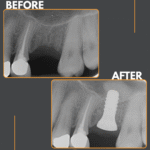

A week of implants @ Charlton Road Dental